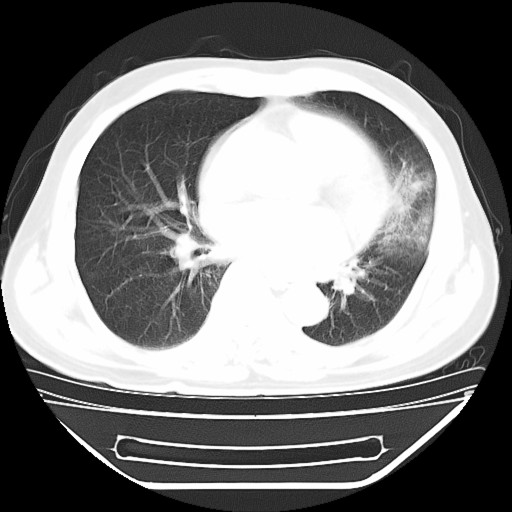

以下是引用hhcckk在2009-5-29 10:34:00的发言:[br]左下肺片絮状边缘模糊影,考虑感染,建议治疗后复查[br]